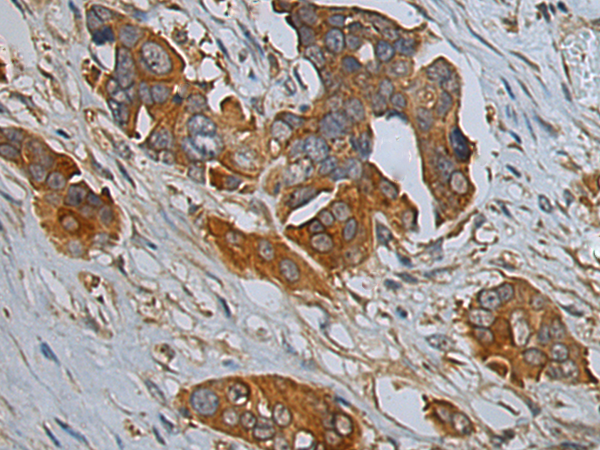

IHC positive control: |

Human colorectal cancer and Human esophagus cancer |

IHC Recommend dilution: |

100-300 |